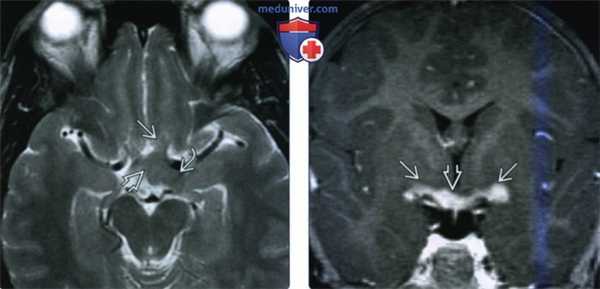

(Слева) При МРТ Т2ВИ в аксиальной проекции определяется глиома зрительною пути, поражающая внутричерепной прехиазмальный сегмент зрительного нерва, хиазму и левый зрительный тракт. Глиомы зрительного пути, как правило, характеризуются более интенсивным Т2-сигналом, чем это изоинтенсивное новообразование.

(Справа) У пациента с двусторонними глиомами зрительною пути при МРТ Т1 с КУ в корональной проекции определяется яркое контрастирование хиазмы и проксимальных сегментов обоих зрительных трактов. Глиомы зрительного пути демонстрируют крайне вариабельное контрастное усиление.

(Слева) При МРТ Т1ВИ с КУ в аксиальной проекции определяется диффузное расширение прехиазмальных сегментов обоих зрительных нервов и хиазмы лишь при минимальном неравномерном контрастировании. Двусторонние ГЗП обычно свидетельствует о наличии у пациента НФ1.

(Справа) При МРТ Т2ВИ в аксиальной проекции головною мозга определяется округлое высокоинтенсивное новообразование базальных ганглиев, что типично для НФ 1. Значимого контрастирования этих новообразований не наблюдается.